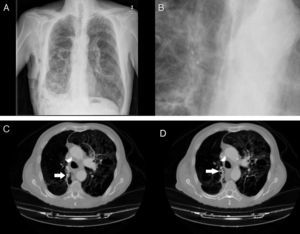

La válvula se introduce mediante un catéter a través del canal de trabajo del broncoscopio y al liberarla se autoexpande, anclándose a la mucosa bronquial (fig. 2A y B).

Durante todo el procedimiento se monitoriza cuidadosamente la profundidad de la anestesia y las constantes vitales, y al finalizar su colocación se realiza una radiografía de tórax (fig. 3A y B), o una TC si fuera necesario (fig. 3C y D) para descartar complicaciones, constatar la reexpansión pulmonar y su correcto enclave.

A)Radiografía de tórax con válvulas IVB en lóbulo superior derecho. B)Detalle de la radiografía de tórax con válvulas IBV en lóbulo superior derecho. C)TC de tórax en paciente con enfisema bulloso y válvula IBV colocada en B2 derecho (señalada por fecha). D)TC de tórax en paciente con enfisema bulloso y válvula IBV colocada en B1 derecho (señalada por flecha). Paciente con neumotórax derecho y enfisema pulmonar (paciente n.¿ 5).